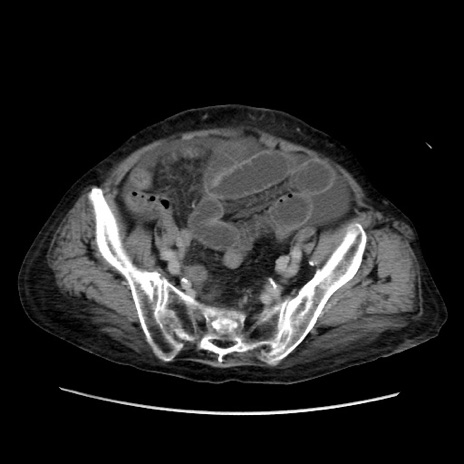

症例31(横断像)

【症例】80歳代 女性

【主訴】腹部膨満感

【現病歴】他院にて肝硬変にてフォロー中。1週間前から便秘、腹部膨満感、臍部腫瘤あり受診となる。

【既往歴】肝硬変

【身体所見】腹部膨隆あり、皮膚変化なし、疼痛なし。

【データ】WBC 4600、CRP 0.25